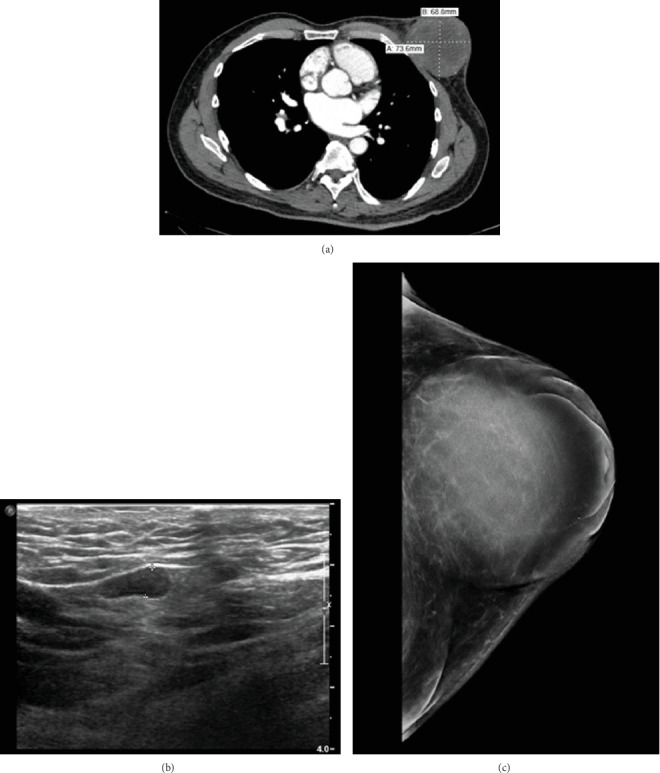

Encapsulated papillary carcinoma (EPC) is an invasive carcinoma which shows papillary architecture within a thickened fibrous capsule. Multiple studies have shown that this tumor follows an indolent course with excellent prognosis, and as such, it is recommended that it be staged as in situ lesions. It is an uncommonly encountered tumor most often diagnosed in postmenopausal females. As breast cancer in males is overall rare, available data on diagnosis, management, and outcomes of EPC in males is limited. Typically, cases of EPC that present with advanced stage and/or lymph node metastases show an associated invasive process. We present a case of pure EPC in a male patient with associated skin ulceration and positive lymph nodes, leading to a final stage of ypT4bN1a. The present report underscores the indolent nature of EPC, even when diagnosed at an advanced stage.